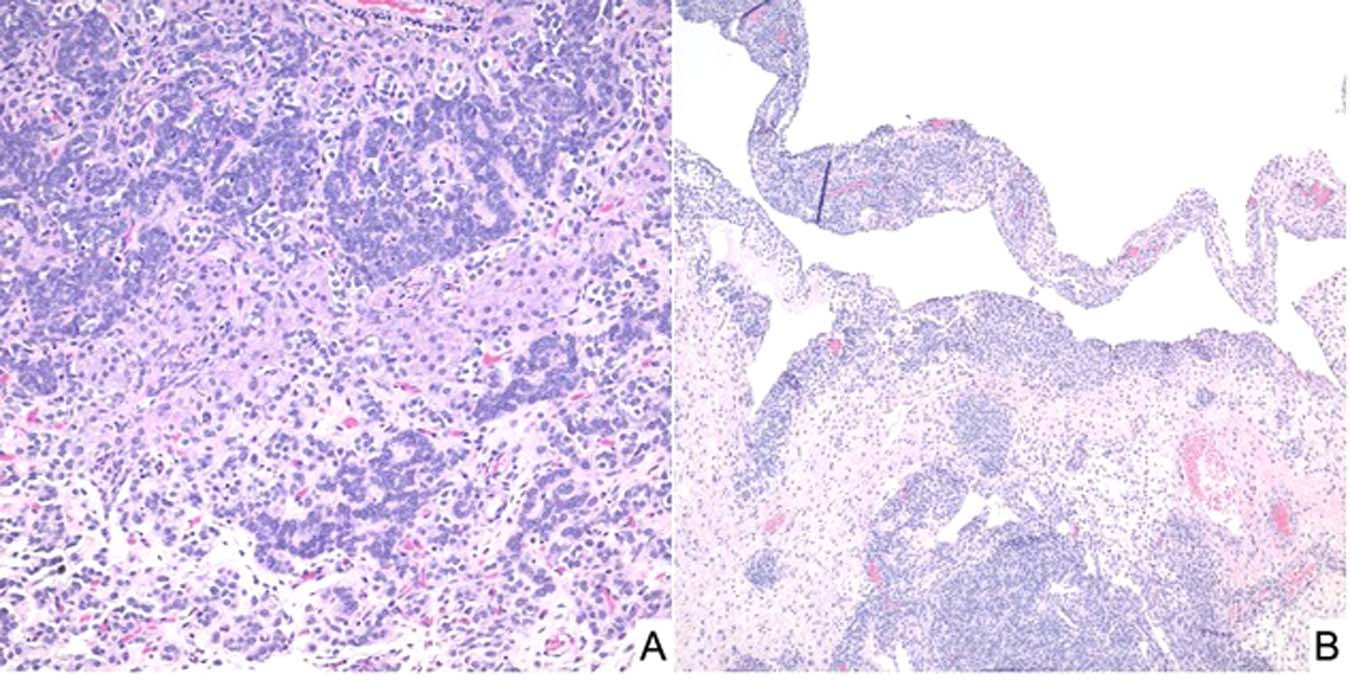

Fig. 7: Sertoli-Leydig cell tumor, moderately differentiated in an adolescent presenting with an abdominal mass.

A Solid foci of this solid and cystic mass showing groups of Sertoli cells and surrounding Leydig cells. B Cystic focus with a delicate septum with a cambium layer-like localization of Sertoli cells with its resemblance to PPB type I.